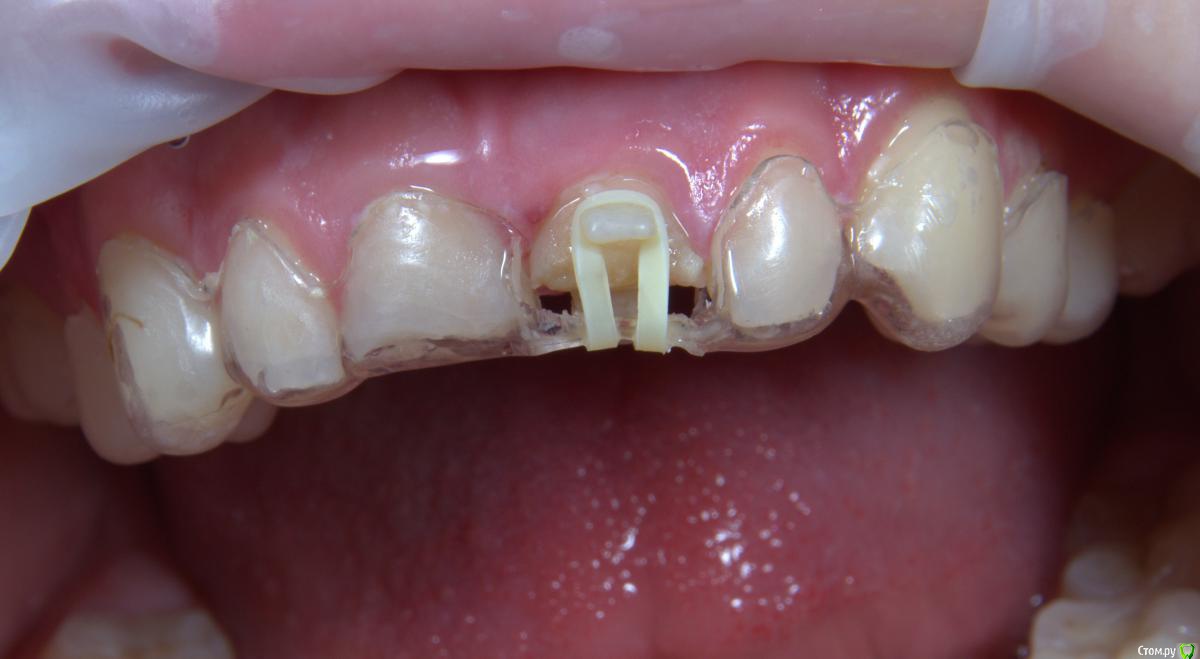

Хью Крейн Опубликовано 11 августа, 2017 Поделиться Опубликовано 11 августа, 2017 Композит на небной поверхности не мешает окклюзии? Ссылка на комментарий

kamranchick Опубликовано 11 августа, 2017 Автор Поделиться Опубликовано 11 августа, 2017 Композит на небной поверхности не мешает окклюзии?мешает, а как быть?) Ссылка на комментарий

Art 7 Опубликовано 11 августа, 2017 Поделиться Опубликовано 11 августа, 2017 ставишь стекловолоконную балку между апроксимальных поверхностях соседних зубов) Ссылка на комментарий

kamranchick Опубликовано 11 августа, 2017 Автор Поделиться Опубликовано 11 августа, 2017 ставишь стекловолоконную балку между апроксимальных поверхностях соседних зубов)Спасибо Артурчик)Попробуем так))) просто шатается сильно, страшно трогать пока что) Ссылка на комментарий

1586Doc Опубликовано 11 августа, 2017 Поделиться Опубликовано 11 августа, 2017 (изменено) Это обычная силиконовая каппа ?вытягиваем, потом стабилизация ? Как на долго? Изменено 11 августа, 2017 пользователем 1586Doc Ссылка на комментарий

kamranchick Опубликовано 11 августа, 2017 Автор Поделиться Опубликовано 11 августа, 2017 Это обычная силиконовая каппа ?вытягиваем, потом стабилизация ? Как на долго?капу сделали вакуум формером, помоему она пластмассовая вроде. стабилизация 2-3 месяца... Ссылка на комментарий